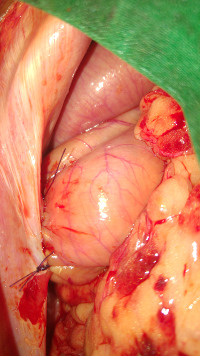

Luxation glande Harder

-enfouissement Gl.Harder lors de luxation (methode Morgan)